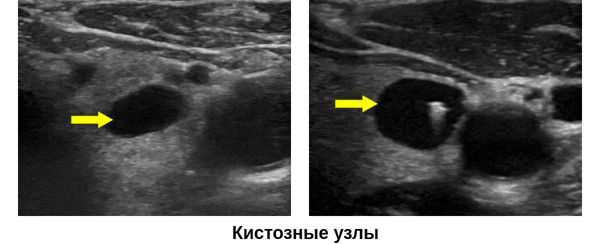

Основным методом диагностики является УЗИ щитовидной железы. На УЗ-картине кисты представлены в виде образований правильной формы с ровными, тонкими стенками и анэхогенным (не отражающим звук), гомогенным содержимым, которые имеют капсулу. Позади кисты присутствует акустический эффект усиления сигнала, что также подтверждает жидкое содержимое кисты.